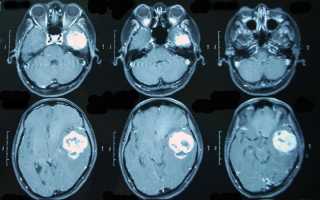

Чтобы выявить опухоль головного мозга, необходимо пройти несколько диагностических процедур, назначаемых неврологом и офтальмологом. Проводится УЗИ, КТ и МРТ головного мозга. Эти процедуры относятся к неинвазивным методам обследования. К инвазивным причисляют биопсию – забор тканей с последующим гистологическим анализом. Важнейшей частью диагностики является исключение других патологий, связанных с появлением опухолей головного мозга. На основании результатов обследования будет подобрана схема лечения.

Профилактика саркомы головного мозга заключается в исключении воздействия провоцирующих факторов, ведении здорового образа жизни, регулярном прохождении обследования. С помощью КТ и МРТ можно обнаружить новообразование любого типа, размера и локализации. Раннее начало лечения существенно увеличивает шансы на выздоровление.